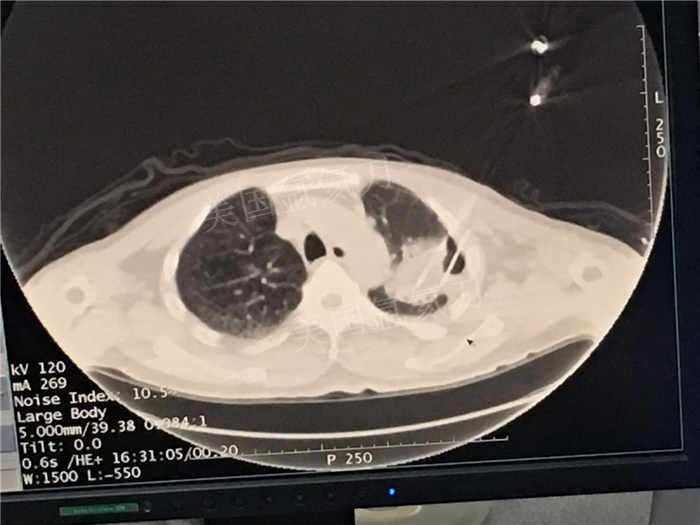

发布人:美国氩氦刀技术官方网站 发布时间:2018/7/5 10:57:23

下一篇:中日友好医院氩氦刀冷冻消融治疗胸膜间皮瘤